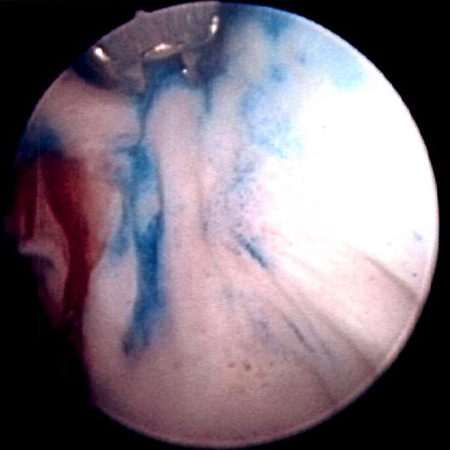

[Figure caption and citation for the preceding image starts]: Methylene blue-stained tumor at the right bladder neck. Staining with 0.2% methylene blue (or use of the now Food and Drug Administration-approved hexaminolevulinate blue-light fluorescence cystoscopy) can help identify tumors not seen otherwiseFrom the collection of Donald Lamm, MD, FACS [Citation ends].

Low-grade tumors are papillary and easy to visualize, but high-grade tumors can be papillary, flat, or in situ and difficult to visualize with white light. Visualization at cystoscopy may be improved by narrow-band imaging or blue light (fluorescence) cystoscopy in addition to white light; both appear to improve diagnostic accuracy compared with white light alone.[40]American Urological Association. Diagnosis and treatment of non-muscle invasive bladder cancer: AUA/SUO joint guideline. 2024 [internet publication].

Features suggestive of noninvasive (Ta) disease include papillary tumors having a narrow stalk. Invasive tumors more commonly have a thick stalk or solid configuration. Rough erythematous patches can be indicative of Tis (carcinoma in situ), although urothelium often appears normal. Random biopsies or biopsy of areas positive on blue light or narrow band cystoscopy are needed to properly diagnose Tis.[59]Bhindi B, Kool R, Kulkarni GS, et al. Canadian Urological Association guideline on the management of non-muscle-invasive bladder cancer - Full-text. Can Urol Assoc J. 2021 Aug;15(8):E424-60.